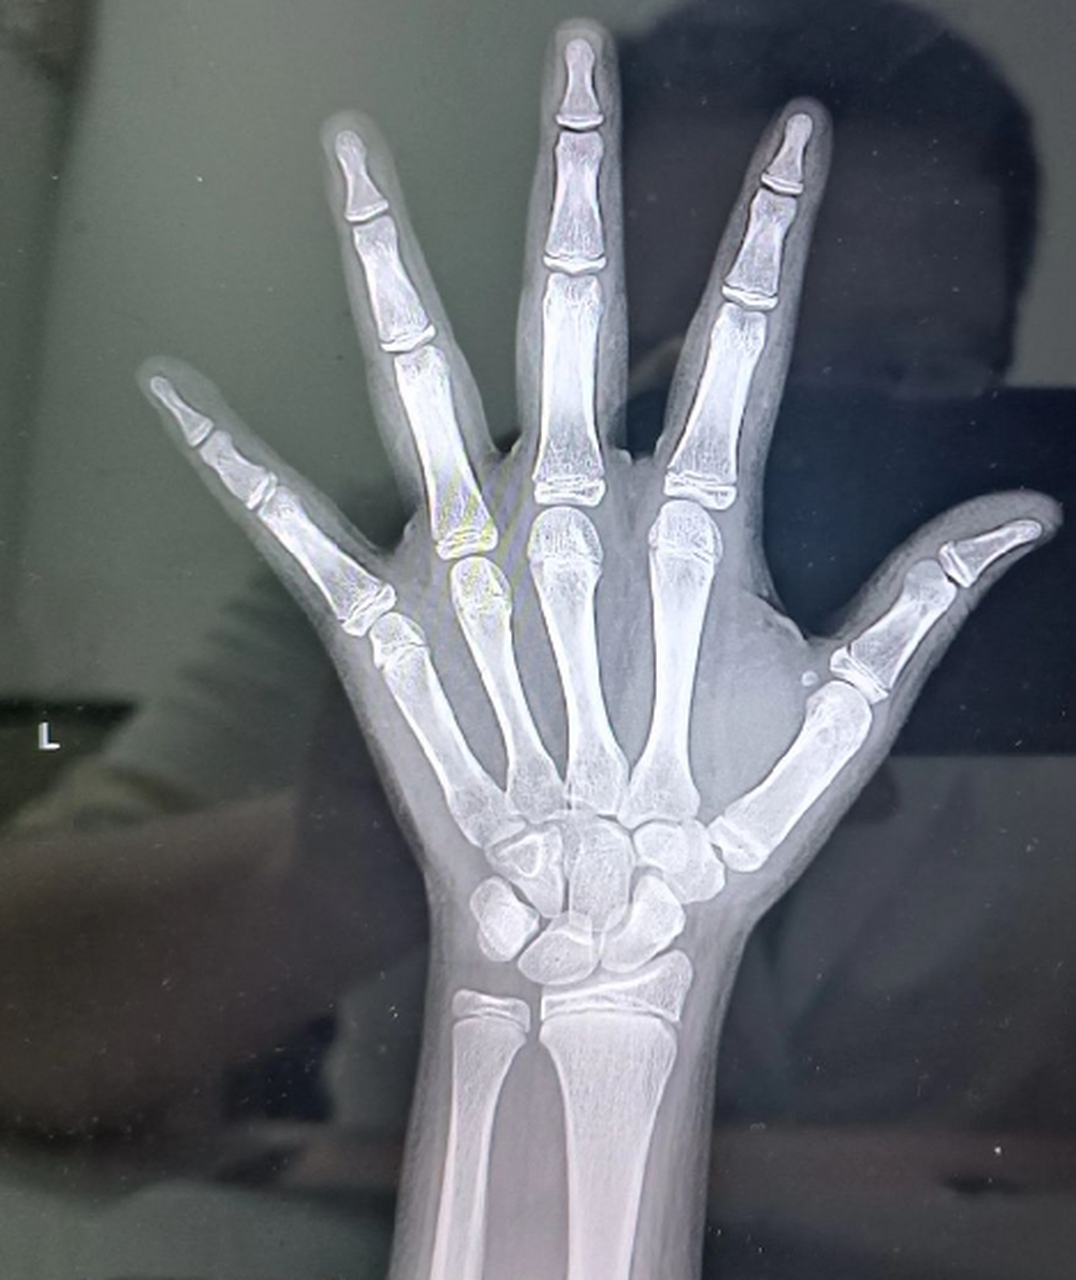

麻烦传一张没有闭合骨骺线的手的x光片

图片尺寸1600x1200